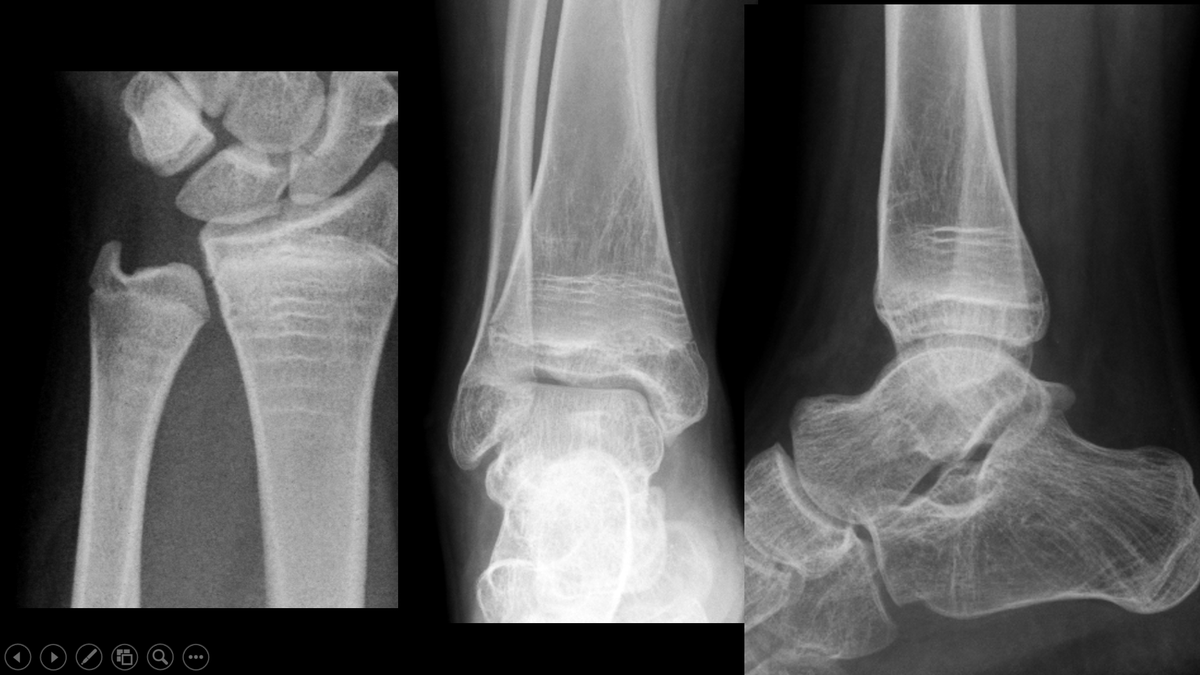

🔔 ¡Ya puedes inscribirte al VII Curso SER de Osteoporosis y Patología Metabólica Ósea! #OP25 🗓️ Tendrá lugar el 26 y 27 de septiembre, en #Madrid, con la colaboración de ucb_iberia, bajo la coordinación de los Dres. Enrique Casado y Laia Gifre. 📝 ser.es/evento/curso-s…